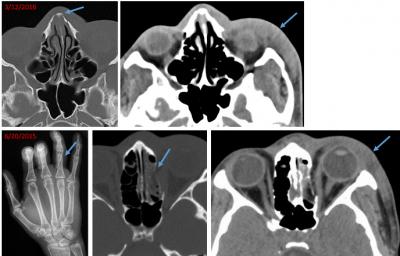

The case that inspired the principal investigator Bharti Khurana, MD, involved a young woman who presented to the Emergency Department with an acute nasal bone fracture superimposed on an old healed fracture. While going through prior studies of the patient on the hospital's picture archiving and communication system, or PACS, she came across a recent wrist fracture. This pattern of recurrent injury made her raise the suspicion for intimate partner violence, a finding the referring physician initially had not suspected.

On evaluation, common patterns of injury emerged from the team's research. These included soft tissue injuries (swelling, hematoma or contusion) and extremity fractures, often involving the distal upper extremities, suggesting injury from defensive attempts. Another commonly seen injury was facial fractures. On a clinical front, the team also identified that IPV victims often present with physical or psychologic symptoms that were not directly related to the abuse, thereby reinforcing the need for screening protocols to identify these patients. IPV victims in the study were more likely to be homeless, while the sexual assault victims often suffered from illicit drug abuse.

The team presented data as well as anecdotes illustrating that radiology images may detect violence months or even years before a patient seeks help.

"Images do not lie and can sometimes tell us more than the patient in this situation," said Khurana. "In the emergency room setting, the priority is to identify acute pathologies, and hence old fractures or fracture-related deformities may not be given sufficient importance. But the presence of old and acute fractures may be pivotal in making the diagnosis of IPV."